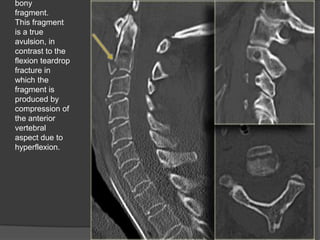

Extention tear drop fracture

AVULSION FRACTURE of anterio inferior content

of the axis resulting from hyperextention

 This injury is



stable in flexion

but highly unstable in extension.

common in diving accidents

 It also may be associated with the central cord

syndrome .

bony

fragment.

This fragment

is a true

avulsion, in

contrast to the

flexion teardrop

fracture in

which the

fragment is

produced by

compression of

the anterior

vertebral

aspect due to

hyperflexion.